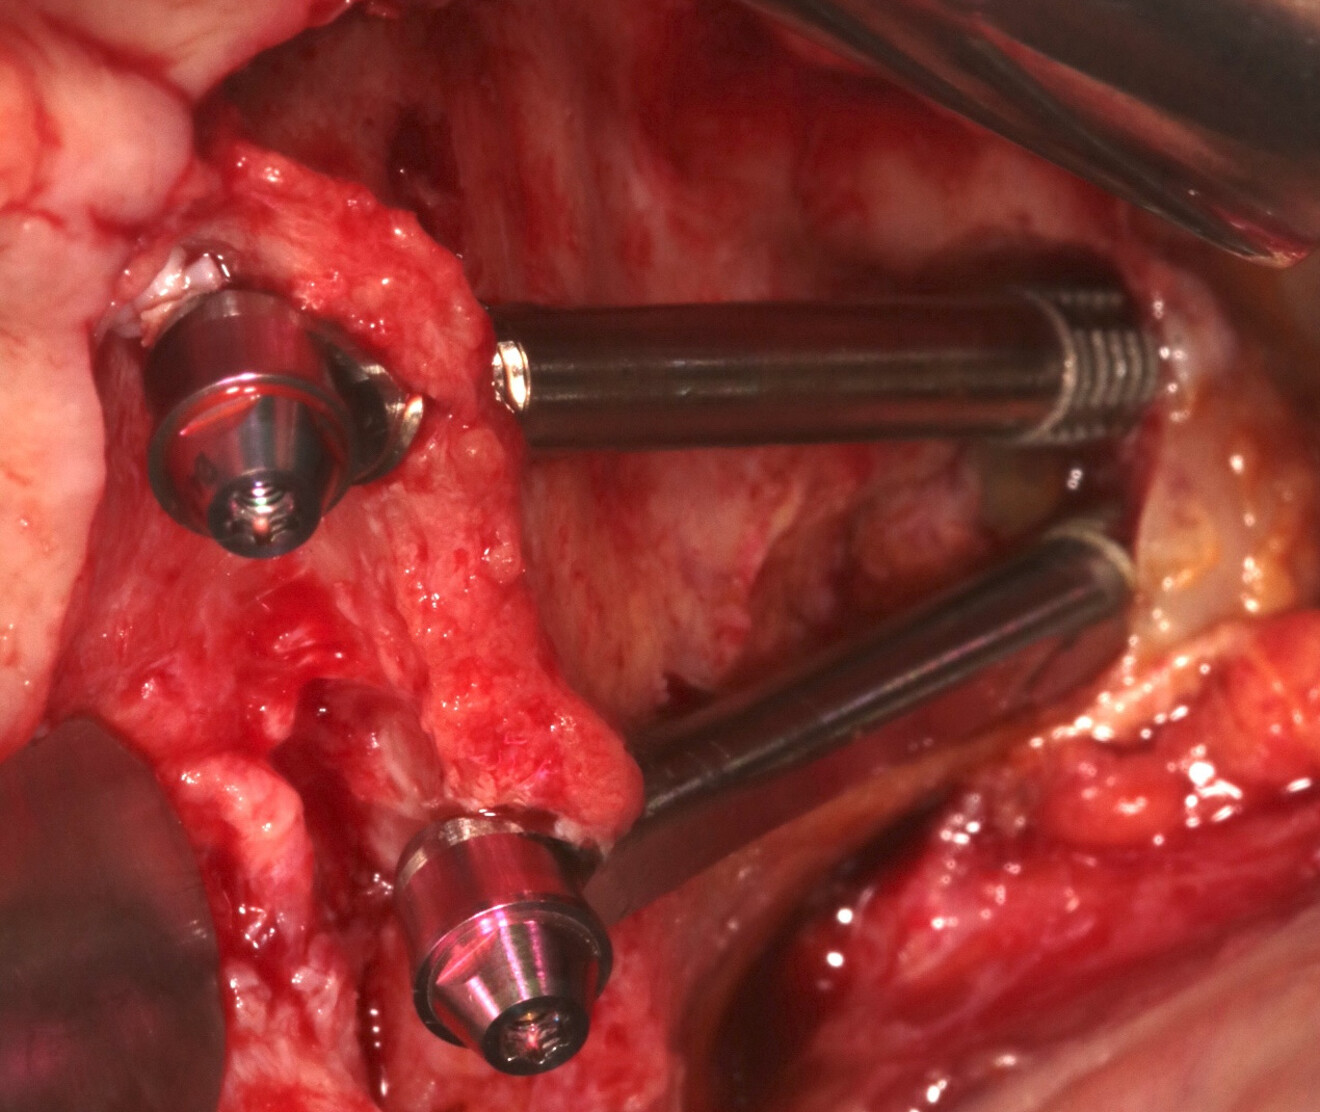

Fig. 1a : Photographie endobuccale de deux IZ.